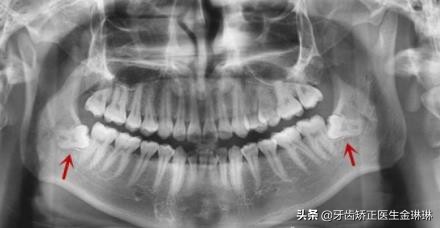

不过具体是否需要拔除,一般需要根据医生建议进行的,可能也有位置比较正的智齿是不需要拔除的,但是如果真的是位置正,就不会出现炎症,也不会疼痛了,所以大部分智齿就诊的患者,通常都是需要拔除智齿的。

智齿不需要一次性全部拔除,分几次进行拔除痛苦更小一些,因为智齿拔除难度比较大,拔牙后一两天会有严重的疼痛和脸部对应位置的肿胀,如果是同侧两颗牙齿或者是单颗智齿拔除,不会影响另一侧咀嚼和进食,所以这是比较好的。建议大家可以采用这样的方式。诺尔漫齿科在看诊定价收费上一直按照物价标准定价以及坚持透明化收费,所有费用一目了然,不存在隐形消费,患者只花该花的钱,看牙就诊更明细清楚。